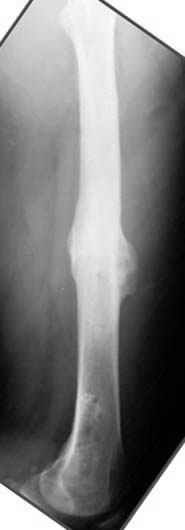

Несколько снимков из моей коллекции, чтобы разьяснить, почему мы до сих пор делаем различные варианты остеотомии.

На рисунке N1 предоперационный план лечения ложного сустава шейки бедра- линия ложного сустава, угол и направление введения импланта, клиновидная остеотомия в градусах и миллиметрах, второй снимок после коррекции, расчет, на сколько удлиняется конечность и размеры импланта;

N3 рисунок окончательный снимок, после операции моя рентгенограмма должен выглядеть примерно как эта картина. На N4 снимке клин перед удалением; N5 послеоперации 3 нед.; N6 окончательная рентгенограмма.

пластическая модель; и коррекция бедра аппаратом Илизарова.